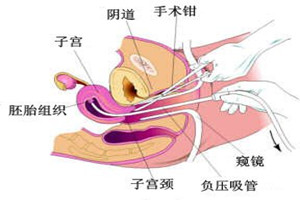

2、准确定位:手术全程由可视超导技术引导,在显示屏幕上直接观察宫腔内部的状况,确定孕囊的位置,对绒毛进行定点的吸引。可视让手术更加安全,避免不当的操作,医生看着屏幕做手术,准确性高。

3、安全性高:无痛人流的创伤更小、术后恢复快、更安全、不影响再次孕育。传统的人流采用的吸管材料是金属做的,很容易损伤宫内组织,而无痛人流采用的一次性宫腔组织吸引管,对宫内组织损伤小,避免了术后粘连、感染等问题。可视技术减少了宫内的损伤,避免并发症的出现。

4、成功率高:采用可视技术,大幅度提高了手术的成功率,传统的人工流产是依靠医生的临床经验对宫腔进行刮宫,无法窥视宫腔内部的状况,很容易导致子宫穿孔,人流不全、漏吸、出血、感染等多种并发症,甚至造成宫腔粘连、月经紊乱,而无痛人流彻底克服了这些缺点。